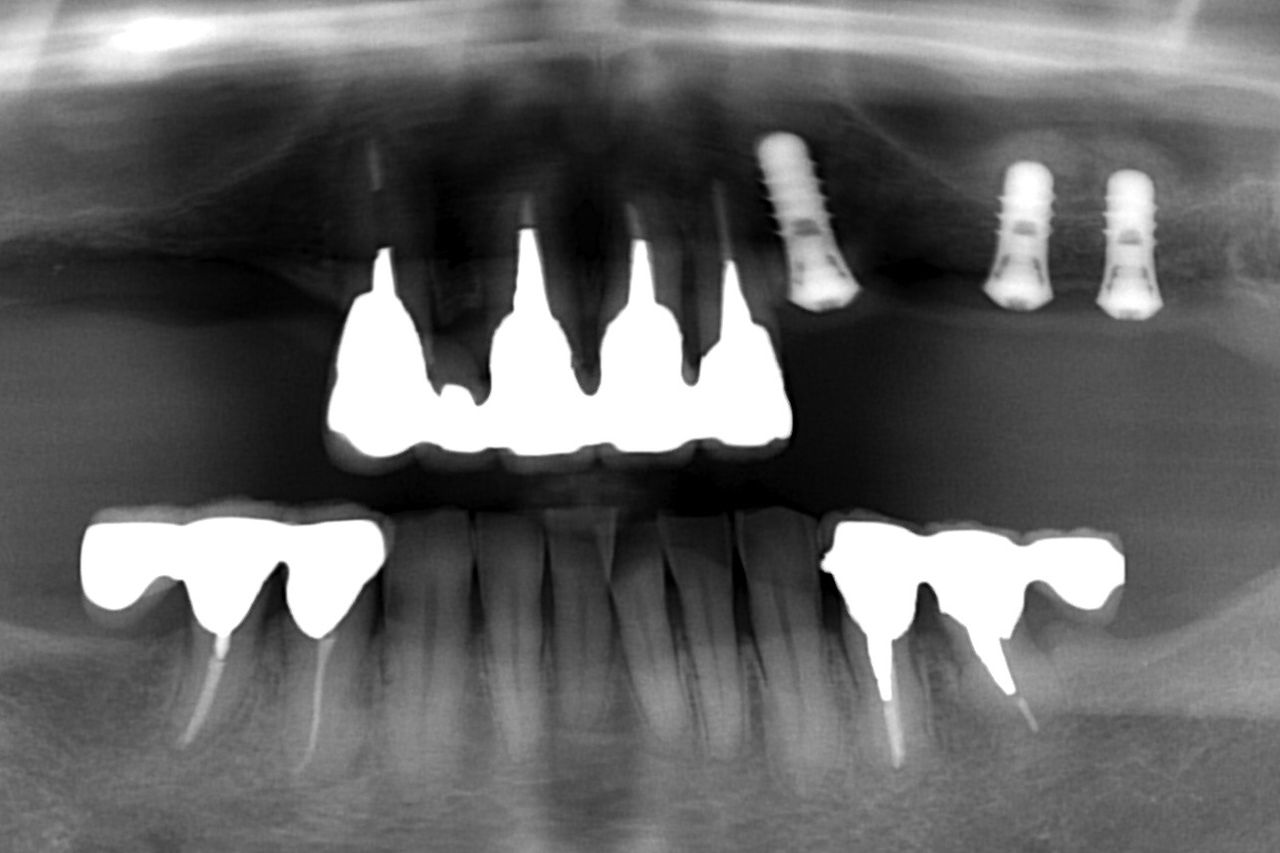

それでは、早速初診時のレントゲンから始めましょう!

今回問題が起こっているのが、上顎の左側です。

上顎左側の歯肉が時々腫れるとのことで来院されました。

歯根破折 している部位を拡大して見てみましょう!

以下の黄色まるの部分が歯根破折した歯です。

歯の真ん中で割れているのが分かると思います。

(見慣れていないと少し分かりづらいかもしれません。

竹を縦に割ったように完全に2つに分離しています)

以下は抜歯後です。

いつものように 骨吸収の状態を分かりやすくするために

骨吸収の状態を線で書いたのが以下のレントゲンになります。

青線が骨吸収を起こす前の骨の位置です。

赤線は、現在の骨の位置です。

骨吸収はさほどありません。

まだ、抜歯した部位の穴が残っているだけです。

問題となったのが、上顎洞の存在です。

以下の緑線は上顎洞という空洞です。

緑線の内側は空洞なのです。

骨ではありません。

ただの 穴 です。

以下のレントゲンは、ソケットリフト法 を応用してインプラントを埋入した直後です。

次に治療前後のレントゲン比較を見てみましょう!

左側が治療前です。

右側がインプラント手術直後です。

奥のインプラントの尖端が白っぽく見えると思います。

この白い部分がソケットリフト法 によって上顎洞内部に入れた人工の骨です。

もう少し分かりやすいように上顎洞とソケットリフト法 によって押し上げられた位置を線で書いてみましょう!